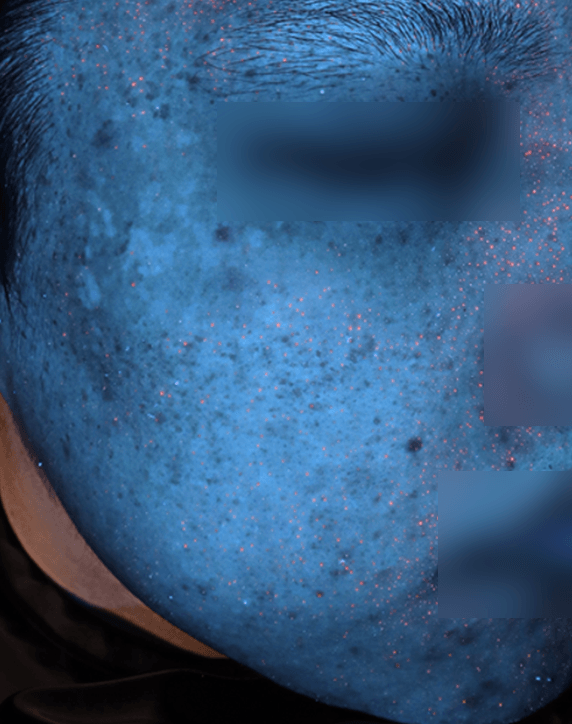

자외선광 1회차 / 10회차

2025.02.24

2025.05.08